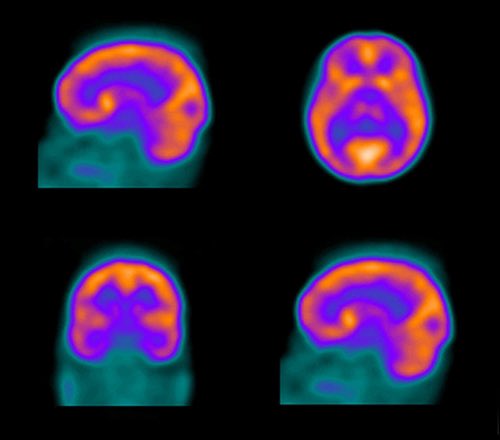

(PET scan ) التصوير المقطعي باالاصدار البزيترني ويعتير من احدث التطورات في المجال ويساعد بفحص النشاط الكيميائي بالجسم ويساهم باكتشاف الامراض في مراحلها الاولى والتي لاتظهر في اجهزة الاشعة مثل السرطانات وانتشارها وامراض القلب والدماغ .